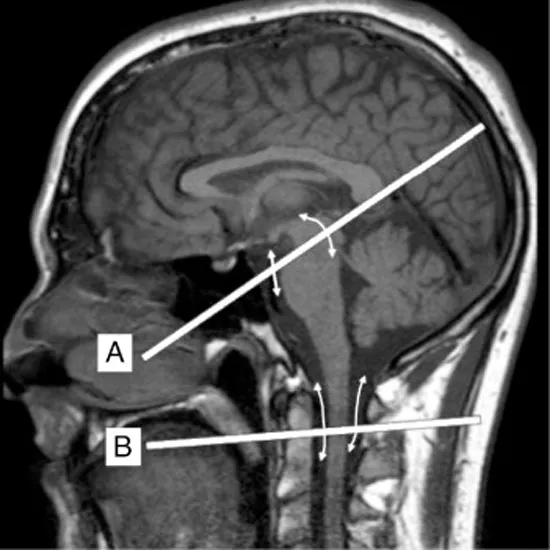

MRI of the brain with CSF Flow study uses magnetic and radio waves for the detection of abnormalities in the cerebrospinal fluid (CSF) in the brain and spinal cord. or spine that estimates the flow of cerebrospinal fluid (CSF) around the brain, brainstem or spinal cord.